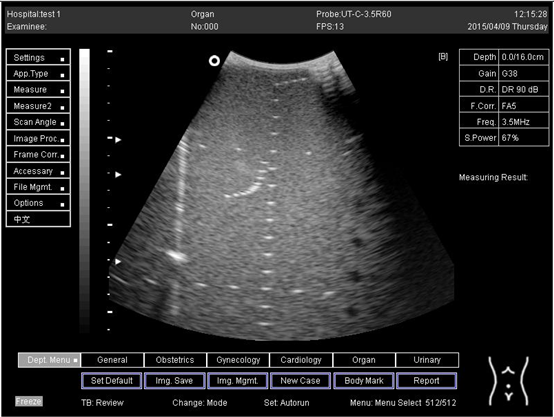

Table A5. The image taken for focal zone determination in different depth for curve probe.

Depth (cm)Diagram

18.0Biomimetics 07 00130 i033